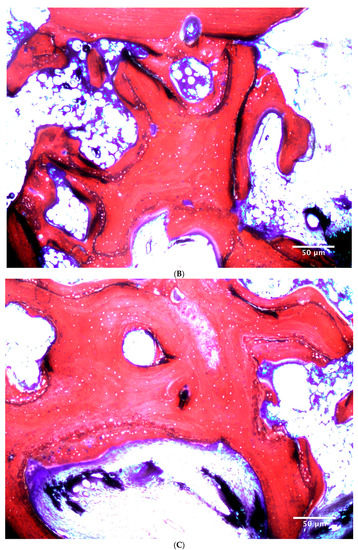

2.10. Histological Preparation and Histomorphometric Evaluation

| NFB | BMSC | 16.0 ± 6.1% | 7.8 ± 6.7% | 11.9 ± 7.5% A |

| ATSC | 9.9 ± 5.4% | 5.3 ± 5.2% | 7.6 ± 5.6% B | |

| MEAN | 12.9 ± 6.4% a | 6.6 ± 5.9% b | - | |

| XRP | BMSC | 20.7 ± 9.9% | 24.1 ± 7.0% | 22.14 ± 8.5% A |

| ATSC | 15.2 ± 4.9% | 28.0 ± 6.3% | 21.6 ± 8.5% A | |

| MEAN | 17.9 ± 8.1% a | 26.1 ± 6.8% b | - | |

| NMT | BMSC | 63.4 ± 10.5% Bb | 68.3 ± 10.3% Aa | - |

| ATSC | 74.8 ± 7.4% Aa | 66.7 ± 7.4% Ab | - |